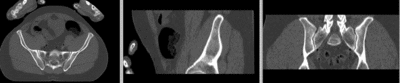

registered (nonrigid+masking) registered (nonrigid+masking)

deformation only of vhf registered deformation only of vhf

deformation grid deformation visualized by grid image overlay